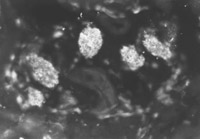

燒傷后7天(圖5-4-4),燒傷后14天(圖5-4-5),在該兩時(shí)間點(diǎn)鏡下可見(jiàn)比燒傷后4天繼續(xù)增多的表皮再生干細(xì)胞。潛在的再生干細(xì)胞即含人角蛋白19型細(xì)胞的數(shù)量達(dá)到燒傷療程中的峰值(數(shù)量最多)。至燒傷后21天(圖5-4-6)和28天(圖5-4-7)兩時(shí)間點(diǎn)潛在再生干細(xì)胞數(shù)量又減至一定的水平。觀察中發(fā)現(xiàn)患者經(jīng)濕性燒傷醫(yī)療技術(shù)治療后,潛在再生干細(xì)胞的增生狀態(tài)有一定的變化規(guī)律。潛在再生干細(xì)胞可能是表皮再生的干細(xì)胞的來(lái)源,這些在熒光顯微鏡下顯示熒光的細(xì)胞是深Ⅱ度和淺Ⅲ度燒傷后還存在的潛在的表皮再生干細(xì)胞。這些細(xì)胞可使燒傷濕性醫(yī)療技術(shù)治療的深Ⅱ度燒傷無(wú)瘢痕愈合,淺Ⅲ度燒傷皮膚再生。

圖5-4-4 經(jīng)MEBT/MEBO治療,燒傷后7天,角蛋白19型陽(yáng)性細(xì)胞數(shù)量達(dá)峰值  ×200

圖5-4-5 經(jīng)MEBT/MEBO治療,燒傷后14天,角質(zhì)蛋白19型陽(yáng)性細(xì)胞數(shù)量達(dá)峰值  ×200

圖5-4-1圖5-4-7均為應(yīng)用小鼠抗人角蛋白19型單克隆抗體于冰凍切片染色(生物素-抗生物素蛋白DSC體系間接免疫熒光)照片。